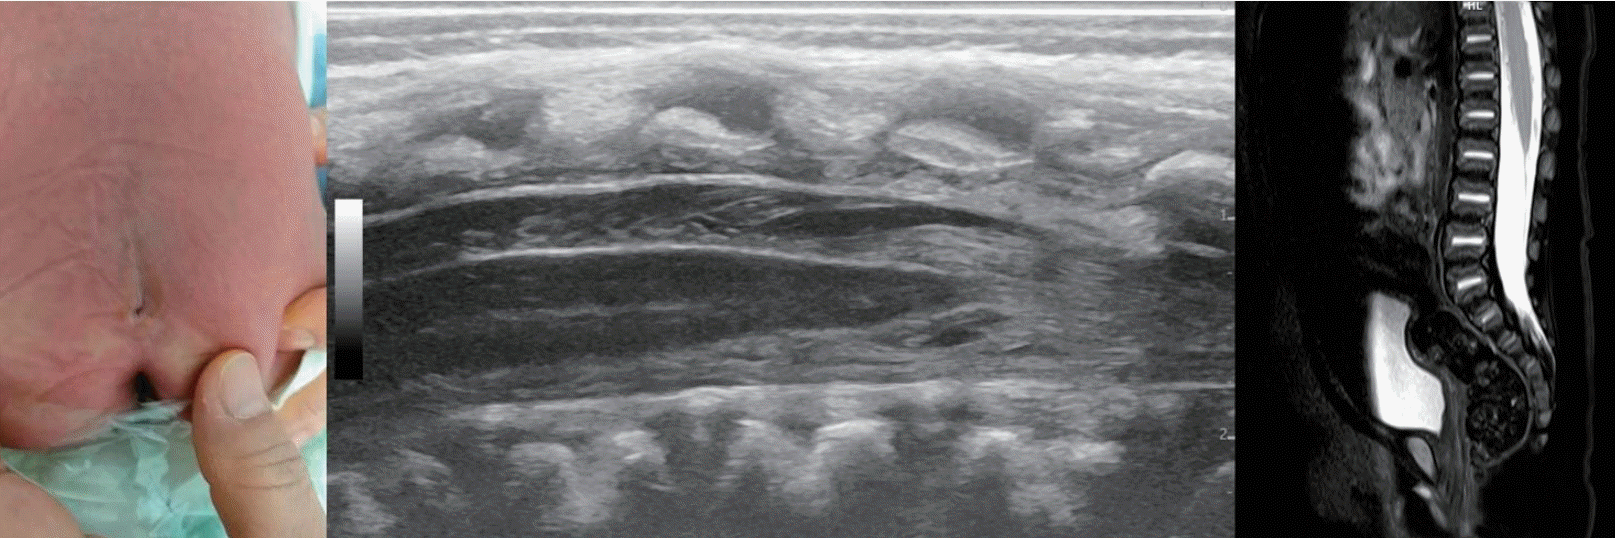

Sacral dimples, also referred to as sacrococcygeal or coccygeal dimples or pits, are the most frequently encountered cutaneous anomalies during neonatal spinal assessments. These dimples present as shallow or deep depressions in the lower sacral region, typically within or near the natal cleft [1]. The prevalence of sacral dimples in newborns is approximately 1.8%–7.2% [2]. Most sacral dimples are benign, particularly those that are less than 0.5 cm in diameter, singular, and located at midline (Fig. 1). In contrast, dimples that are large, deep, located far from the anus, or associated with hair or exhibit discoloration may be indicative of underlying pathology [2]. A simple sacral dimple is defined as a solitary midline lesion less than 5 mm in diameter that is situated within 2.5 cm of the anus and unaccompanied by drainage or associated cutaneous stigmata such as hypertrichosis, hemangiomas, skin tags, or vestigial tails [3]. Importantly, a coccygeal pit is generally considered a normal anatomical variant without communication with intraspinal structures and does not necessitate further imaging (Fig. 2). However, a true sacral dimple may warrant additional evaluation, as it may be a cutaneous marker of occult spinal dysraphism, with tethered cord syndrome being the most clinically significant example. In the screening of sacral dimples, the reported incidence of abnormal underlying pathology is 0%–3.4% [4,5].

A stepwise diagnostic approach to suspected spinal dysraphism should be guided by evidence-based criteria to determine the need for imaging. Spinal ultrasonography is widely recommended as the initial screening modality for infants with atypical sacral dimples, particularly those younger than 4–6 months of age, before ossification of the posterior elements limits acoustic windows [5]. It is favored as an initial tool because of its high sensitivity and specificity (both approximately 96%) as well as its safety and cost-effectiveness (Fig. 4A) [5,23,24]. Nevertheless, recent evidence indicates that a routine ultrasonographic screening may not be necessary in cases of isolated, simple sacral dimples that lack high-risk cutaneous markers [3,21,23]. The feasibility of spinal ultrasonography in neonates is attributed to incomplete ossification of the posterior vertebral arch, a normal feature of infancy, and the osseous defects seen in spina bifida, both of which allow sound wave penetration and adequate visualization of the spinal canal [25].

Persistent terminal ventricle

Historically known as the “fifth ventricle,” the persistent terminal ventricle (PTV) is a small, ependyma-lined cavity located within the conus medullaris (Fig. 5). While it is often observed in postmortem examinations, it is only detectable on MRI once it reaches a certain size. Embryologically, PTV results from incomplete regression of the terminal ventricle during secondary neurulation that retained continuity to the central canal of the spinal cord. PTV is typically asymptomatic, but there have been rare cases of marked cystic enlargement associated with symptoms such as low back pain, sciatica, and bladder dysfunction. It remains uncertain whether these symptomatic enlargements represent developmental variants or acquired pathological changes due to obstruction within the terminal ventricle. Radiologically, PTV can be distinguished from hydromyelia by its distinct location just above the filum terminale and from intramedullary tumors by the absence of contrast enhancement on gadolinium-enhanced MRI. Notably, cystic structure size typically remains stable on follow-up imaging studies [37].